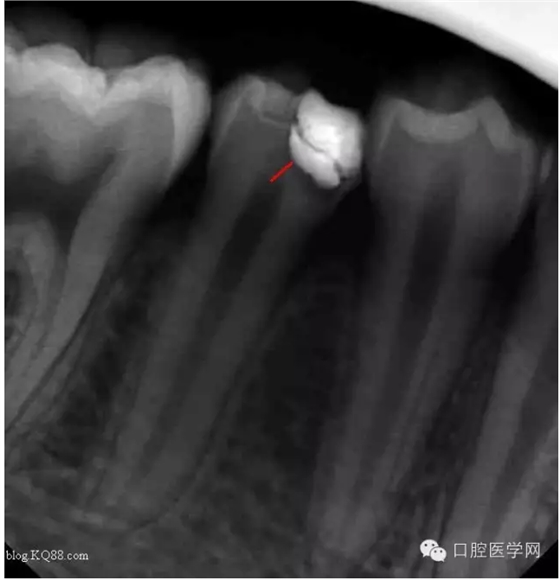

三個月后復(fù)查:高聳的髓角消失。形成約1mm的修復(fù)性牙本質(zhì)?;佳罒o癥狀,溫度測試同對照牙。此時修復(fù)性牙本質(zhì)的形成已趨于穩(wěn)定。每次復(fù)查的溫度測試是判斷牙髓活力,有時雖然沒有臨床癥狀,但牙髓受到慢性刺激會無痛性漸進性壞死。導(dǎo)致保存活髓失敗。

所以每次復(fù)查的溫度測試必不可少的。

最后的充填我是這樣做的:去除部分暫封物。直接樹脂充填。